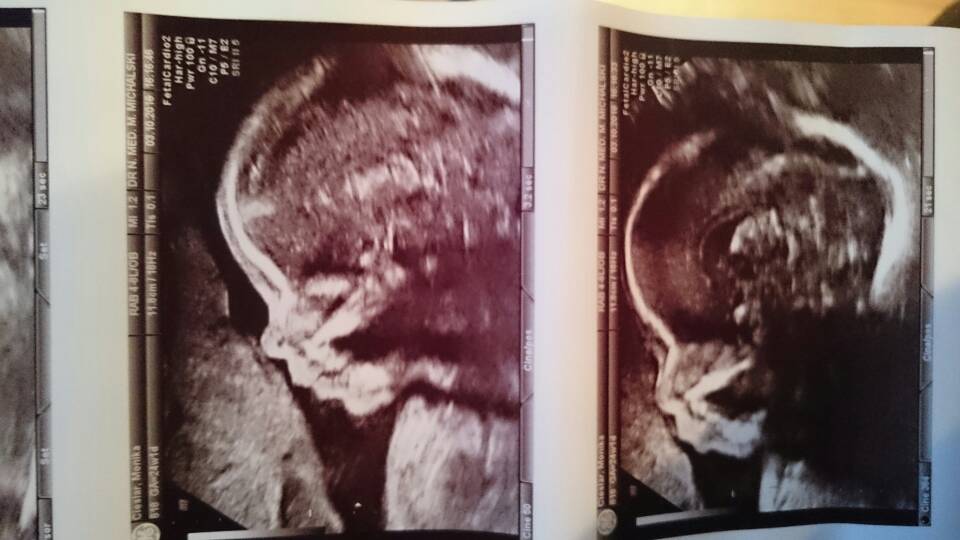

U nas też wszysyko dobrze [emoji2] Lili zostaje Lilianką na 200% [emoji7] gin robił zbliżenie na siśkę i wyraźnie pokazywał mi ze tam już siusiak nie ma szans się pojawić [emoji23] maleńka waży cale 700g i leży poskladana jak scyzoryk z rękami i nogami na głowie [emoji16] i to wyjaśnia dlaczego ruchy czuję doslownie wszędzie [emoji6] mam się powoli przymierzyć do wypicia glukozy przed następną wizytą. Z gorszych wieści z wymazu bakteriologicznego pochwy wyszła mi e. coli która nie daje żadnych objawów. Także od dziś aplikuje globulki przez tydzień.

Oto moja kolejna miłość do grobowej deski!! [emoji7]

1475521840006.jpg

1475521847297.jpg

1475521853748.jpg

• 1475521840006.jpg

55 KB · Wyświetleń: 578

• 1475521847297.jpg

47,8 KB · Wyświetleń: 578

• 1475521853748.jpg

24,7 KB · Wyświetleń: 557